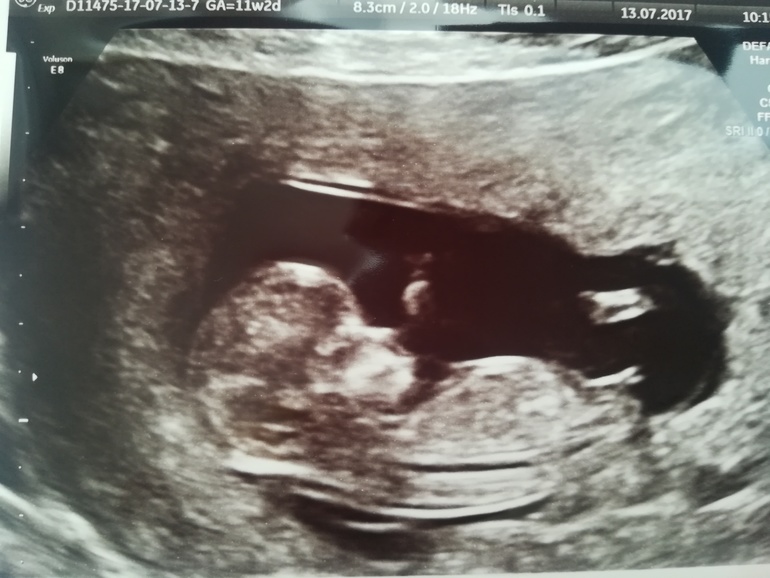

Сегодня был скрининг. По УЗИ все отлично. Опережаем на 2 дня (11/4). КТР 48мм (доча в 11/5 была 39мм) ТВП и носик в норме, ттттт

Прикрепились по передней стенке.

Наше сокровище